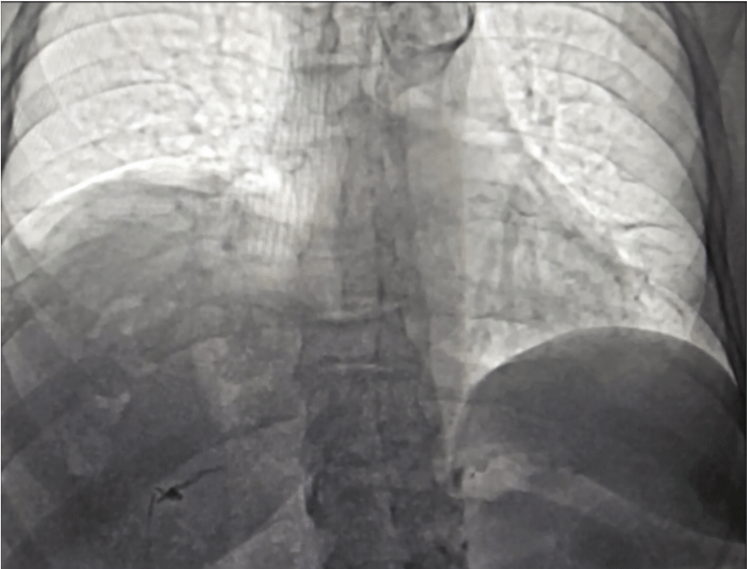

A 73-year-old female presented with typical atrial flutter and paroxysmal AF, requiring repeated cardioversions. She underwent cryoablation of the right atrium and pulmonary veins. No phrenic pacing was conducted during the ablation. At 2-week follow-up, she reported shortness of breath; physical examination revealed decreased breath sounds on the right side. Diagnostic fluoroscopy showed right hemidiaphragmatic elevation (Figure). A nerve conduction study confirmed PNI, showing no right phrenic/diaphragm compound motor action potential. The patient was managed conservatively, and her symptoms improved over the course of 6 months.